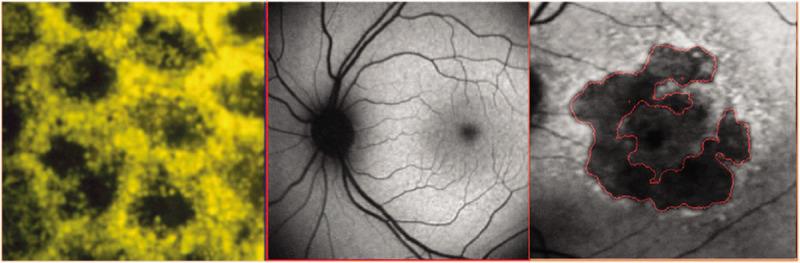

Photoreceptor degeneration tied to lipofuscin accumulation.

As lipofuscin accumulates in the retinal pigment epithelium, photoreceptors degenerate, which leads to vision loss. LBS-008 reduces the production of A2E, which is a toxic component of lipofuscin. Credit: National Eye Institute

Left. Retinal pigment epithelium (RPE) bis-retinoids form complex granules known as lipofuscin, which increase with age, and glow gold under blue light. Middle. Normal gray scale fundus autofluorescence (FAF) image. Right. FAF image of a patient with the dry form of age-related macular degeneration. Credit: Asia Pac J Ophthalmol (Phila). 2020 May-Jun; 9(3): 269–277. Published online 2020 Jun 1.